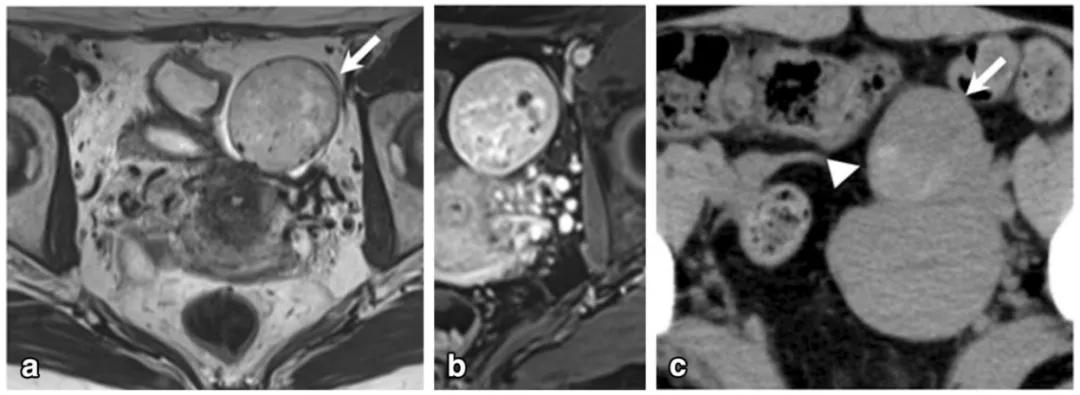

女,50 岁,卵巢甲状腺肿。左卵巢肿物,T2WI 呈不均匀稍高信号(图 a),增强扫描早期明显强化(图 b),CT 扫描显示囊内成份密度稍高(图 c)。